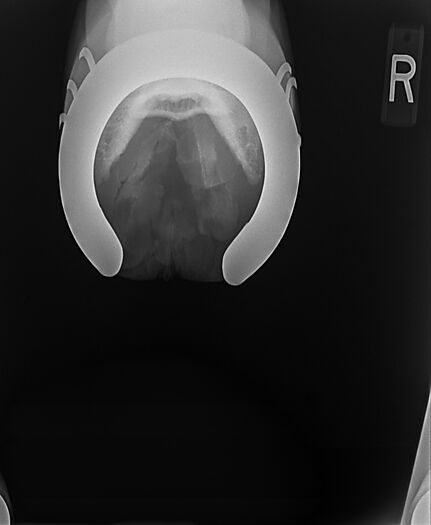

**Tex sells at the Colorado Horse Sale's Best of the West Select Sale on May 30th in Castle Rock, CO - He will complete the riding & handling Sift Exam, baseline veterinary exam, and will sell with 4 total radiographs (DLPMO & Front Foot Lateral)**